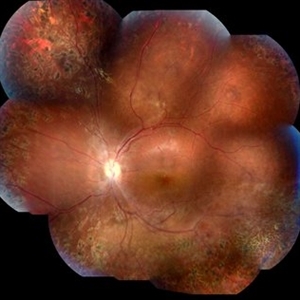

Female patient, 21-years-old, with complaint of low vision in the right eye for 3 years. According to information from the patient's history, at the time she noticed the low vision, it also coincided with a picture of a strong urinary infection as well as episodes of constant tonsillitis. Yes, the patient did not seek medical attention and self-medicated with antibiotics. In ophthalmologic evaluation, as well as examinations of color retinography and ocular fundus autofluorescence, important pigmentary alterations were observed following vascular arches with pigment mobilization in osteoclasts (aspect of a unilateral pigmentary retinitis secondary to the inflammatory process). Which suggested inflammatory process sequelae. Through the laboratory tests, he had positive (+) confirmation for SYPHILIS NEURORETINOPATHY .

Photographer: JEFFERSON R SOUSA - Study Center and Ophthalmological Research Dr. Andre M V Gomes, Institute Dr. Suel Abujamra São Paulo-Brazil

Imaging device: Fundus camera Topcon TRC-50 DX, Imaginet 5.0, angle de 50 graus. Flash 100 / Mosaic with 10 images.

Condition/keywords: autofluorescence imaging, neurosyphilitic optic atrophy, retinitis pigmentosa, syphilis, syphilis neuroretinopathy